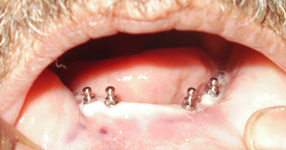

Top Class Treatment

All Types Dental Services